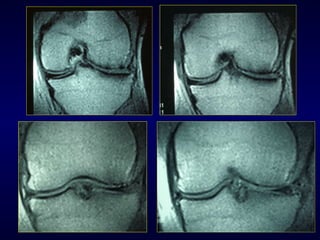

R.M. Nel nostro studio i dati RM non correlano con i risultati La valutazione deve essere soprattutto clinica Comunque la RM deve essere considerata come un buon strumento per valutare il menisco e lo stato della cartilagine

R.M. Nel nostrostudio i dati RM non correlano con i risultati La valutazione deve essere soprattutto clinica Comunque la RM deve essere considerata come un buon strumento per valutare il menisco e lo stato della cartilagine